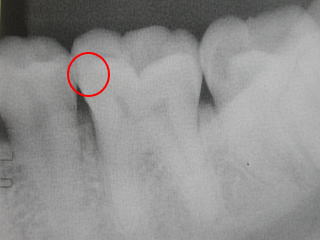

虫歯が発見されました。

小さいので経過を見ることに

なりました。

4年経ちました。

黒い部分が大きくなったきたので

そろそろ削って治療することを考えます。

虫歯の発見から4年削らずにすみました。